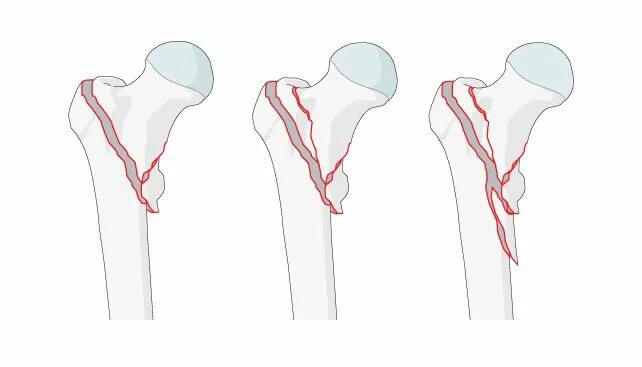

Чрезвертельный перелом без операции